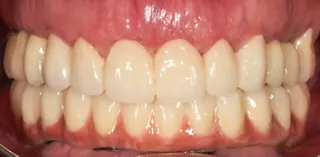

The three scan sets were imported into CAD software, aligned, and used with an implant library to connect the prostheses to titanium bases. A CAD/CAM verification jig confirmed accurate implant position capture. At the second appointment, verification jigs and prototype prostheses were tried in to assess fit, esthetics, phonetics, occlusion, and hygiene access, with minor adjustments as needed. Once approved, the STL files were sent to the lab to fabricate the definitive prosthesis, which consisted of a CAD/CAM-milled monolithic zirconia restoration with a vestibular cut-back to enhance esthetics. The prosthesis was delivered and torqued at the third appointment. The patient reported excellent satisfaction with the treatment, and clinical, intraoral, extraoral, and radiographic examinations revealed no apparent issues (Figs. 17-19).

The patient was followed for 13 months, showing stable functional and esthetic outcomes throughout the follow-up period, with good oral hygiene maintained (Fig. 20).

Treatment outcomes

The patient exhibited stable functional outcomes throughout the 13-month follow-up period, with no signs of implant mobility, peri-implant inflammation, or prosthetic complications. The esthetic result was highly satisfactory, with harmonious integration of the prosthesis into the patient’s smile, natural emergence profiles, and excellent soft tissue support. Both the patient and clinician reported high levels of satisfaction regarding esthetics, phonetics, and masticatory function. The vestibular cutback in the definitive monolithic zirconia restoration enabled enhanced esthetic customization, fully meeting the patient’s expectations.